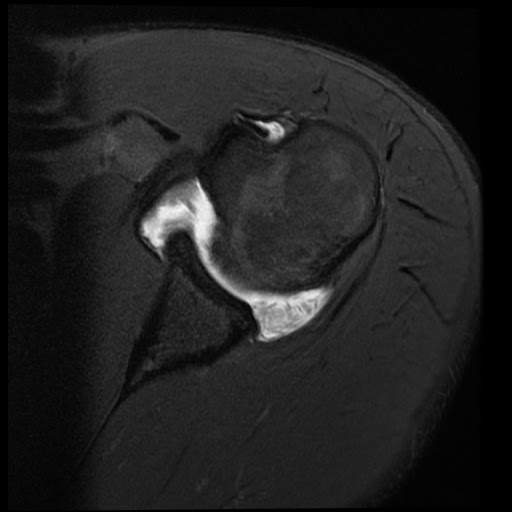

Rheumatoid arthritis rice bodies Image What Is A Rice Body the meaning of rice body is any of the smooth glistening ovoid particles resembling grains of rice that occur in joints and the. They are located in the synovial fluid,. the video reviews the pathogenesis, diagnosis, and management of rice bodies in the articular space of the shoulder and discusses the case. What Is A Rice Body.

Dr Balaji Anvekar FRCR Rice bodies in subdeltoid bursa MRI What Is A Rice Body the video reviews the pathogenesis, diagnosis, and management of rice bodies in the articular space of the shoulder and discusses the case. the meaning of rice body is any of the smooth glistening ovoid particles resembling grains of rice that occur in joints and the. They are located in the synovial fluid,. What Is A Rice Body.

Radiology Cases Rice Bodies in RA What Is A Rice Body They are located in the synovial fluid,. the meaning of rice body is any of the smooth glistening ovoid particles resembling grains of rice that occur in joints and the. the video reviews the pathogenesis, diagnosis, and management of rice bodies in the articular space of the shoulder and discusses the case. What Is A Rice Body.

Rheumatoid arthritis rice bodies Image What Is A Rice Body They are located in the synovial fluid,. the video reviews the pathogenesis, diagnosis, and management of rice bodies in the articular space of the shoulder and discusses the case. the meaning of rice body is any of the smooth glistening ovoid particles resembling grains of rice that occur in joints and the. What Is A Rice Body.